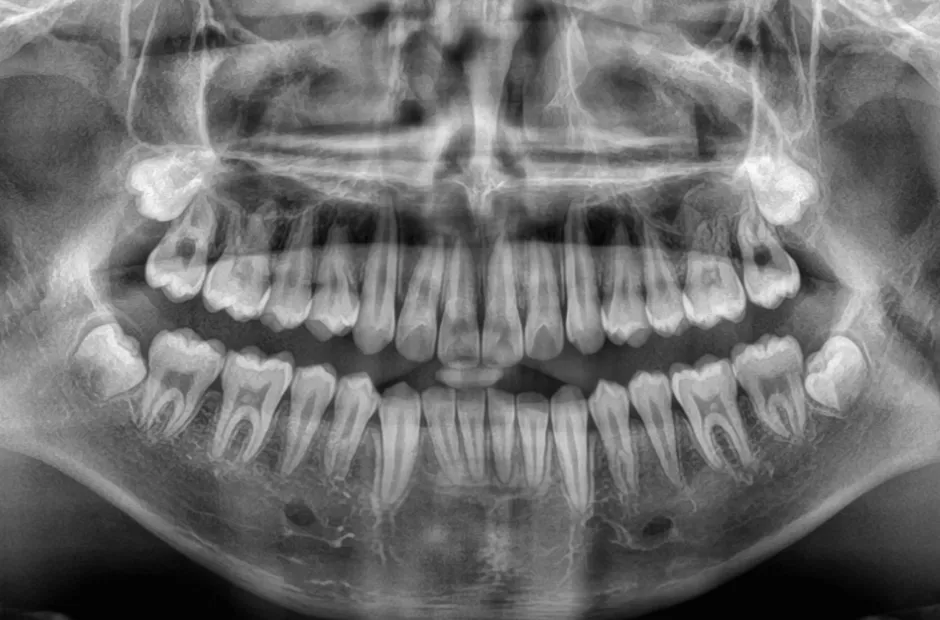

治療後